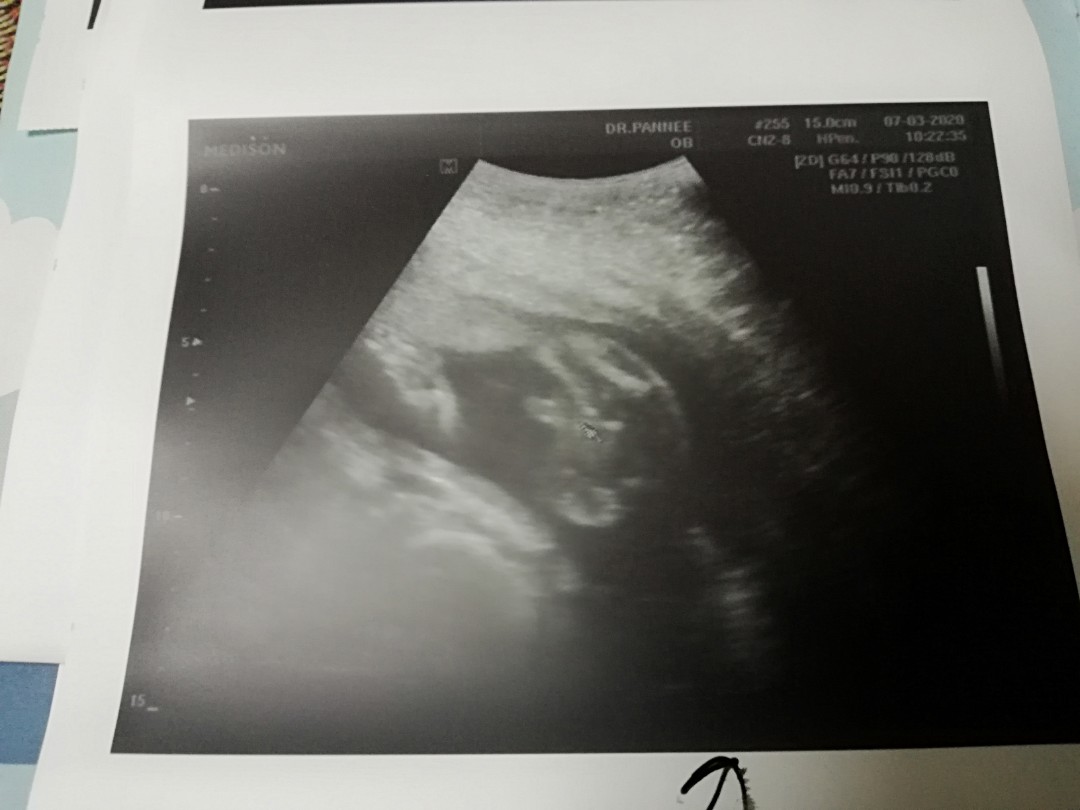

ของบ้านนี้จ้า

หมอบอก ผช. ค่ะ

ชัดเจนค่ะ😁